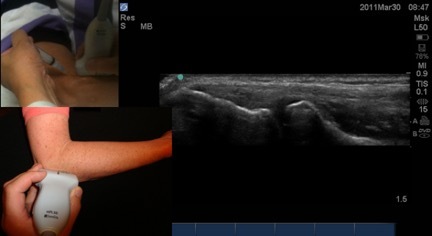

Lateral Elbow Needle Entry Image